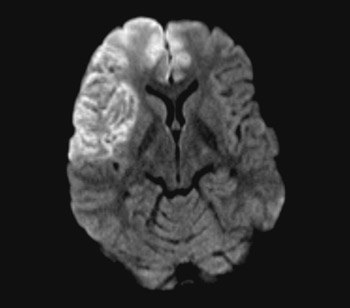

A person in his 20s with known migraine with aura developed infarcts in the right middle cerebral artery and both anterior fields of supply (Figure 1 shows a magnetic tomography diffusion weighted series). Cerebral computed and magnetic tomography with magnetic resonance angiography (MRA) after admission showed normal blood flow and no sign of dissection or vasculitis. Hemicraniectomy became necessary after development of malignant cerebral oedema. MR angiography the first postoperative day showed open arteries (Figure 2 shows an open carotid top (white arrow), normal basilar top (red arrow), and a non-closed circle of Willis, an anatomically normal variant (stars). Testing for illegal drug use, anticardiolipins, anti-nuclear antibodies, neurone antibodies and tumour markers was negative. Transoesophageal echocardiography showed a minimally patent foramen ovale, according to a cardiologic evaluation unlikely to be related to the episode. The patient developed severe brain stem involvement and MR angiography showed narrowing of the posterior branch of the basilar artery (arrows in Figure 3). Arterial vessel spasms were suspected retrospectively. The first suspected vessel spasm, in the right – middle/anterior branch, remained undocumented. The second, in the posterior branch of the basilar artery, was documented postoperatively (arrows in Figure 3). Images of several newly developed infarcts in the posterior circulation are not shown. Three weeks after the hemicraniectomy the angiogram was normalised (Figure 4).